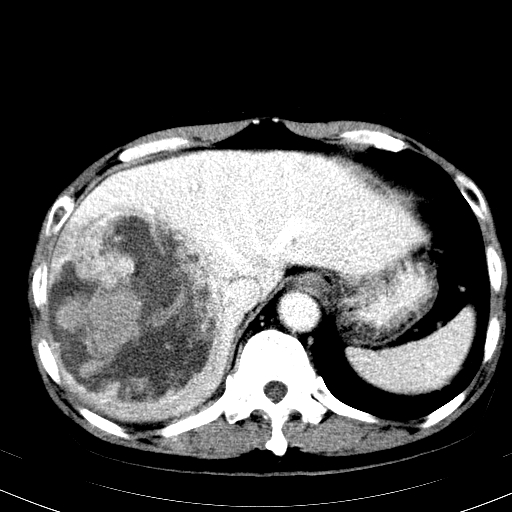

以下是引用卜一在2008-6-23 15:38:00的发言:[br]本例延时期的图象未扫完,单纯平扫 动脉期及门脉期特征分析:平扫低密度较大肿块,内见不规则出血灶,界限清楚。动脉期边缘结节样强化,门脉期病灶边缘进一步强化并范围明显缩小。因此考虑:血管瘤伴出血!

以下是引用hhcckk在2008-6-23 15:10:00的发言:[br]病灶内壁不光滑,中心高密度无强化,考虑肝癌内出血,最后两张横断面是延迟吗?病灶呈低密度。[br][br]鉴别:[br]1、脓肿,内壁光滑,不会发生出血[br]2、血管瘤,早期边缘结节样强化,可合并出血,但延迟后为等密度充填[br]